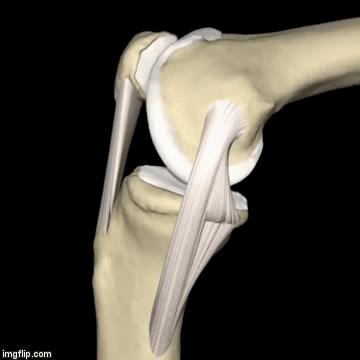

2.其次,再来看一看,当您屈、伸腿时,膝关节具体是怎么移动的?

正常情况下 ,如动图所示,在您屈膝(弯腿)的时候,膝盖骨(俗称菠萝盖)会往内下方移动;而伸膝(伸腿)的时候,膝盖骨会往外上方移动。

一般弹响和膝盖骨的位置运动密切相关;比如说,您的膝盖骨已经靠近膝关节的外侧了,在弯腿的时候,它往内下移动不够,就会在膝盖骨和大腿骨之间摩擦发生弹响。反之,在伸腿时,也是同样的道理。